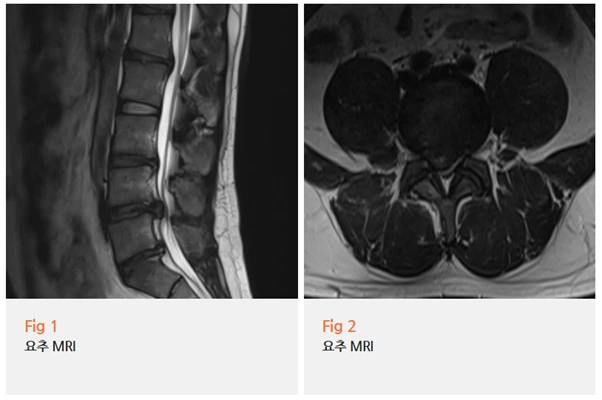

환자분의 MRI를 처음 확인했을 때 순간 숨이 멎는 것 같았어요.

'이게... 20대 척추라고?'

✔️ 요추 4-5번 디스크가 심하게 탈출되어 있었고

✔️ 신경을 직접적으로 압박하고 있었으며

✔️ 다발성 추간판 퇴행이 동시다발적으로 진행 중이었고

✔️ 척추관 협착까지 동반된 상태였어요

근전도 검사 결과도 마찬가지였어요. 복수의 요추 신경근병증이 확인됐죠.